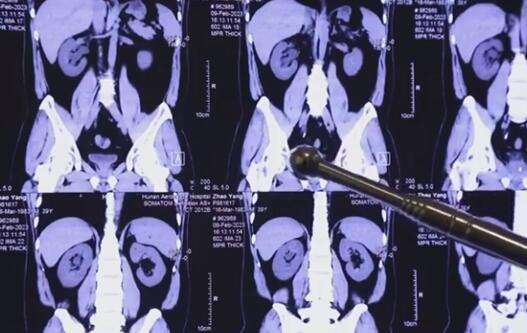

導(dǎo)讀:程序員20年喝近2噸可樂(lè)屢患結(jié)石 原因竟是這樣實(shí)在是太意外了。近日,湖南長(zhǎng)沙。趙先生是一位資深程序員,幾乎天天都喝可樂(lè),二十年來(lái)喝了近兩噸可樂(lè),近期因輸尿管結(jié)石被送進(jìn)醫(yī)院。

據(jù)了解,趙先生患結(jié)石已經(jīng)多年,之前一直沒(méi)當(dāng)回事,今年復(fù)發(fā)檢查后發(fā)現(xiàn)腎臟、輸尿管內(nèi)都有結(jié)石。

經(jīng)手術(shù)治療,目前趙先生體內(nèi)結(jié)石已清除干凈。